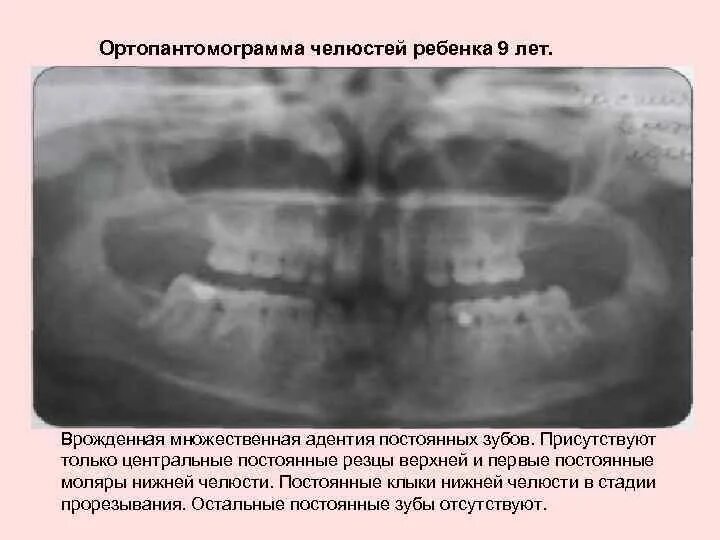

У ребенка нет зачатка постоянного зуба